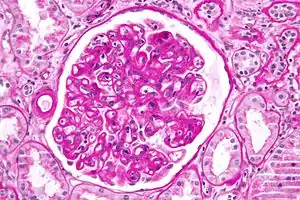

![]() | |

| Micrograph showing lung transplant rejection. Lung biopsy. H&E stain. | |